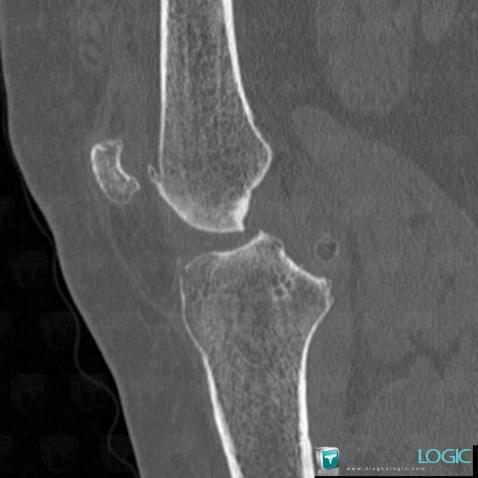

Ostéochondromatose synoviale, Articulations fémoro tibiales / Echancrure, Scanner

Voici les informations spécifiques à l'image clé ci dessus:

- Diagnostic Ostéochondromatose synoviale, Localisation(s) Articulations fémoro tibiales / Echancrure, comportant les gammes Calcification intra ou périarticulaire, Masse des parties molles juxta articulaires, Arthropathie avec nodules des parties molles